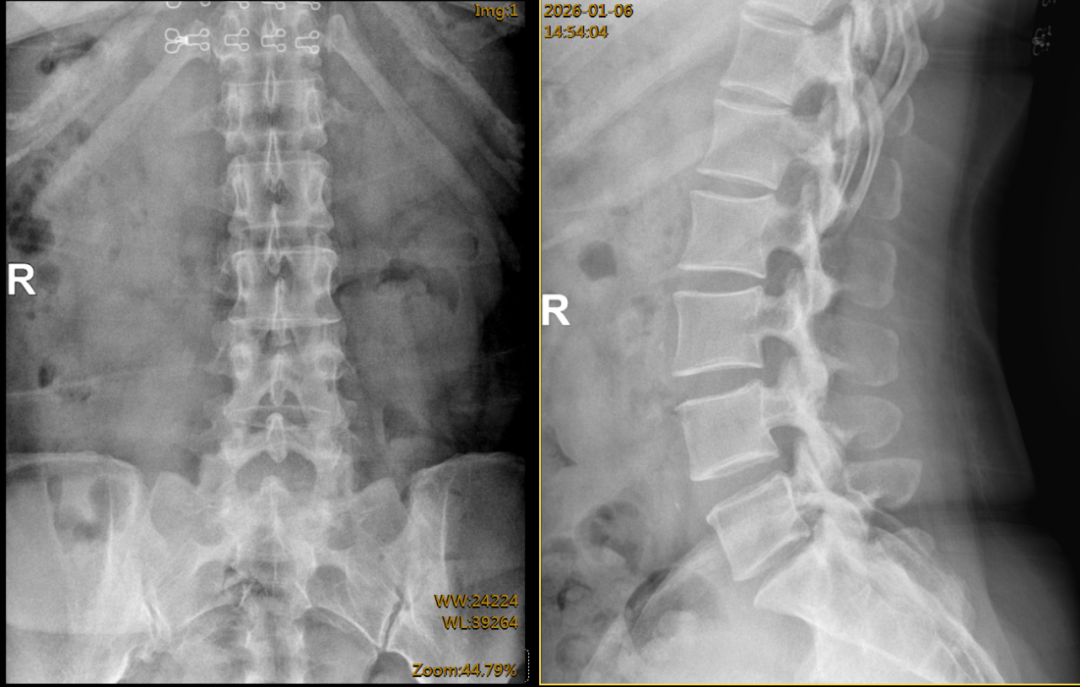

术前腰椎正侧位及动力位片